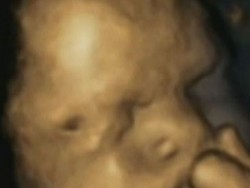

Pronađene do sada nepoznate ćelije koje upravljaju početkom svake trudnoće

Trudnoća